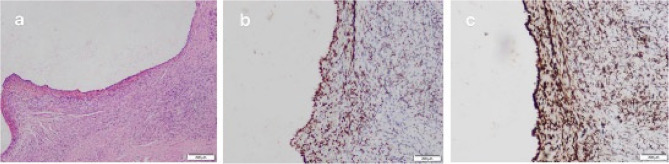

Results: The patient underwent laparoscopic total hysterectomy and bilateral salpingectomy at our hospital more than one year prior because of adenomyosis. No pharmacological treatment was provided postsurgery. One year later, the patient presented with right lumbar discomfort. Imaging revealed hydronephrosis of the right kidney and dilation of the right ureter, leading to a diagnosis of right ureteral endometriosis. Laparoscopic excision of the ureteral endometriotic lesion was performed. Pathology confirmed right ureteral endometriosis with glandular cystic expansion. Postsurgery, the patient was treated with gonadotropin-releasing hormone agonist (GnRH-a) therapy (3.6 mg of goserelin via subcutaneous injection every 28 days for a total of six cycles). Treatment is ongoing. Follow-up ultrasound revealed no abnormalities in the kidneys or ureters, and no recurrence was observed during the five months of follow-up.